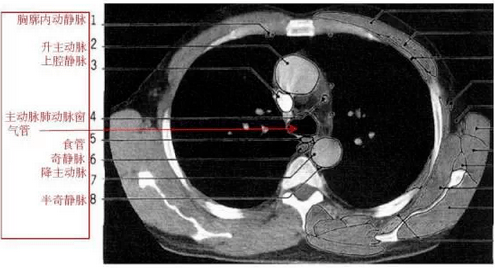

胸部纵隔窗ct高清解剖图谱,附带详细标注

图片尺寸640x670